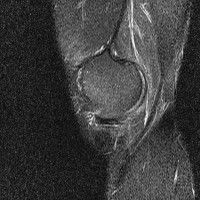

무릎 mri 간단히 봐주실 수 있으시나요 ㅠㅠ

안녕하세요 8년전 십자인대 수술하고 최근 무리한 운동에 무릎 불편감이 생겨서

mri 찍었습니다.

진단결과는 첫 찍은 병원에서 활액막염 이라는 진단을 받았습니다. 혹시 봐주실 수 있으실까요?

올라온 MRI가 단편적이라서 정확한 진단에 어려움이 있지만 십자인대에는 큰 이상이 있지는 않은것 같으며, 무릎관절내 물이 있는 것으로 보아 활액막염의 진단이 맞을 것 같습니다.

하지만 단편적인 영상이기 때문에 촬영병원에서 정확한 판독지 등을 받으시는 것이 좋겠습니다.